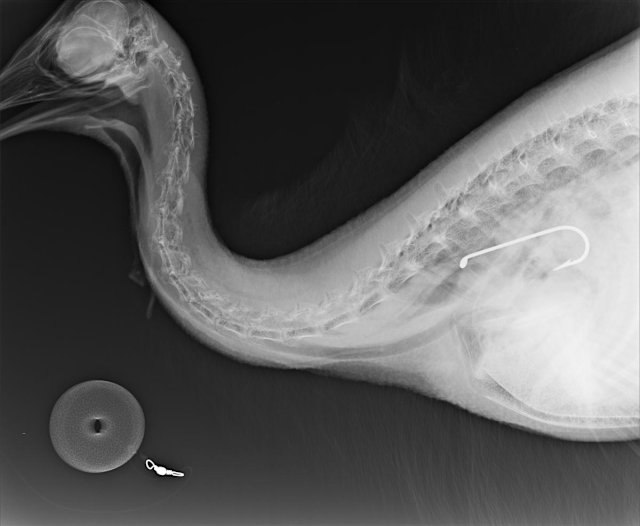

Wildlife rangers at Coquette Point on Queensland’s Cassowary Coast made futile attempts to save the juvenile bird, which had swallowed a fishing hook that became lodged below its throat.

An X-ray examination revealed the extent of the internal damage, and the bird eventually died.